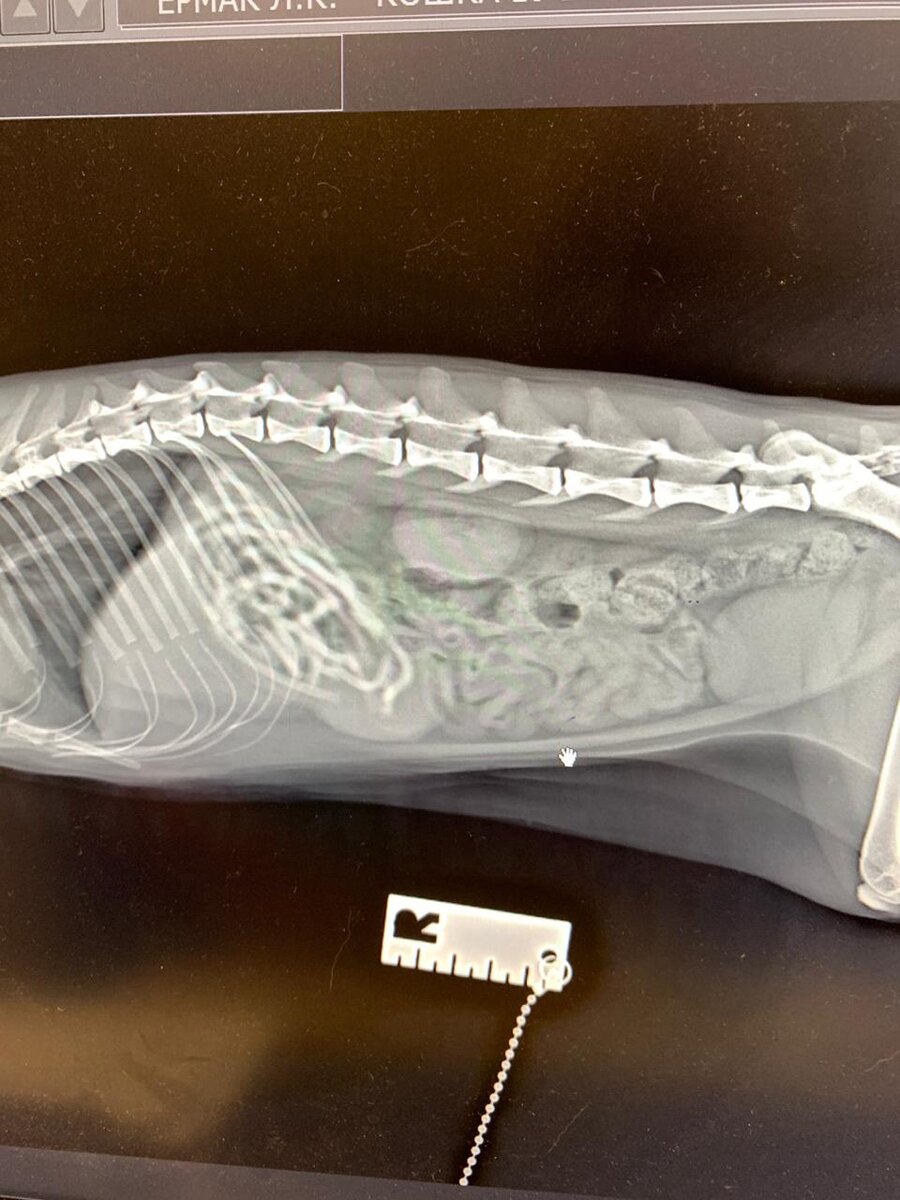

Не давайте кошкам есть резинки